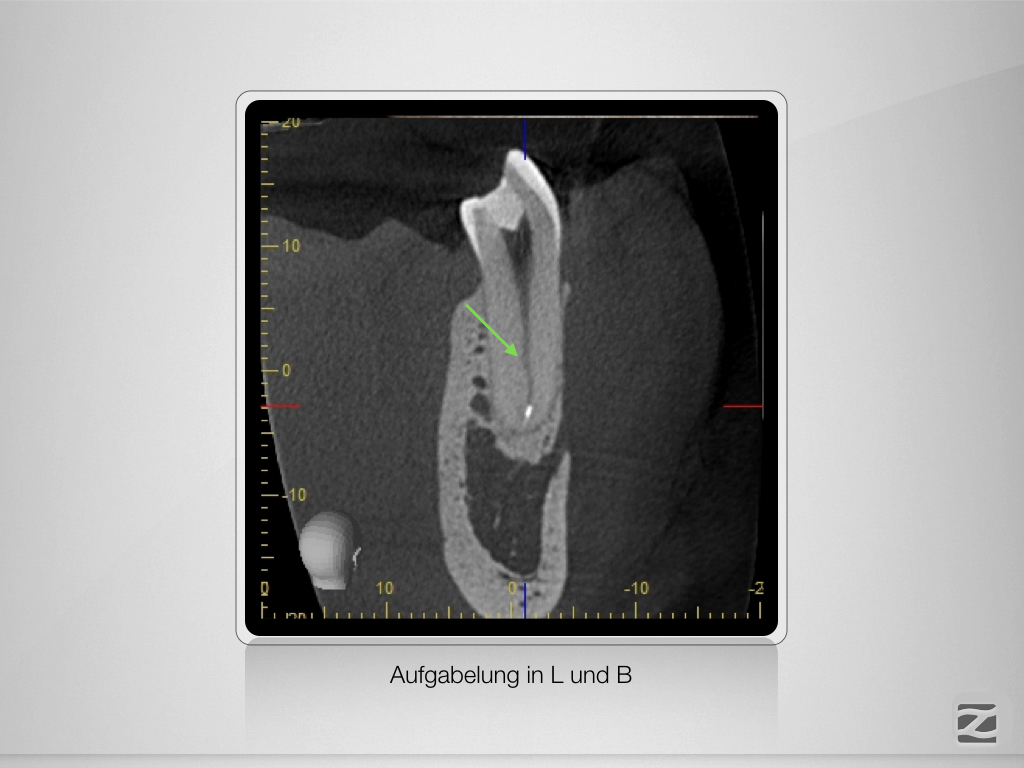

Prämolaren sind (nicht) einfach!